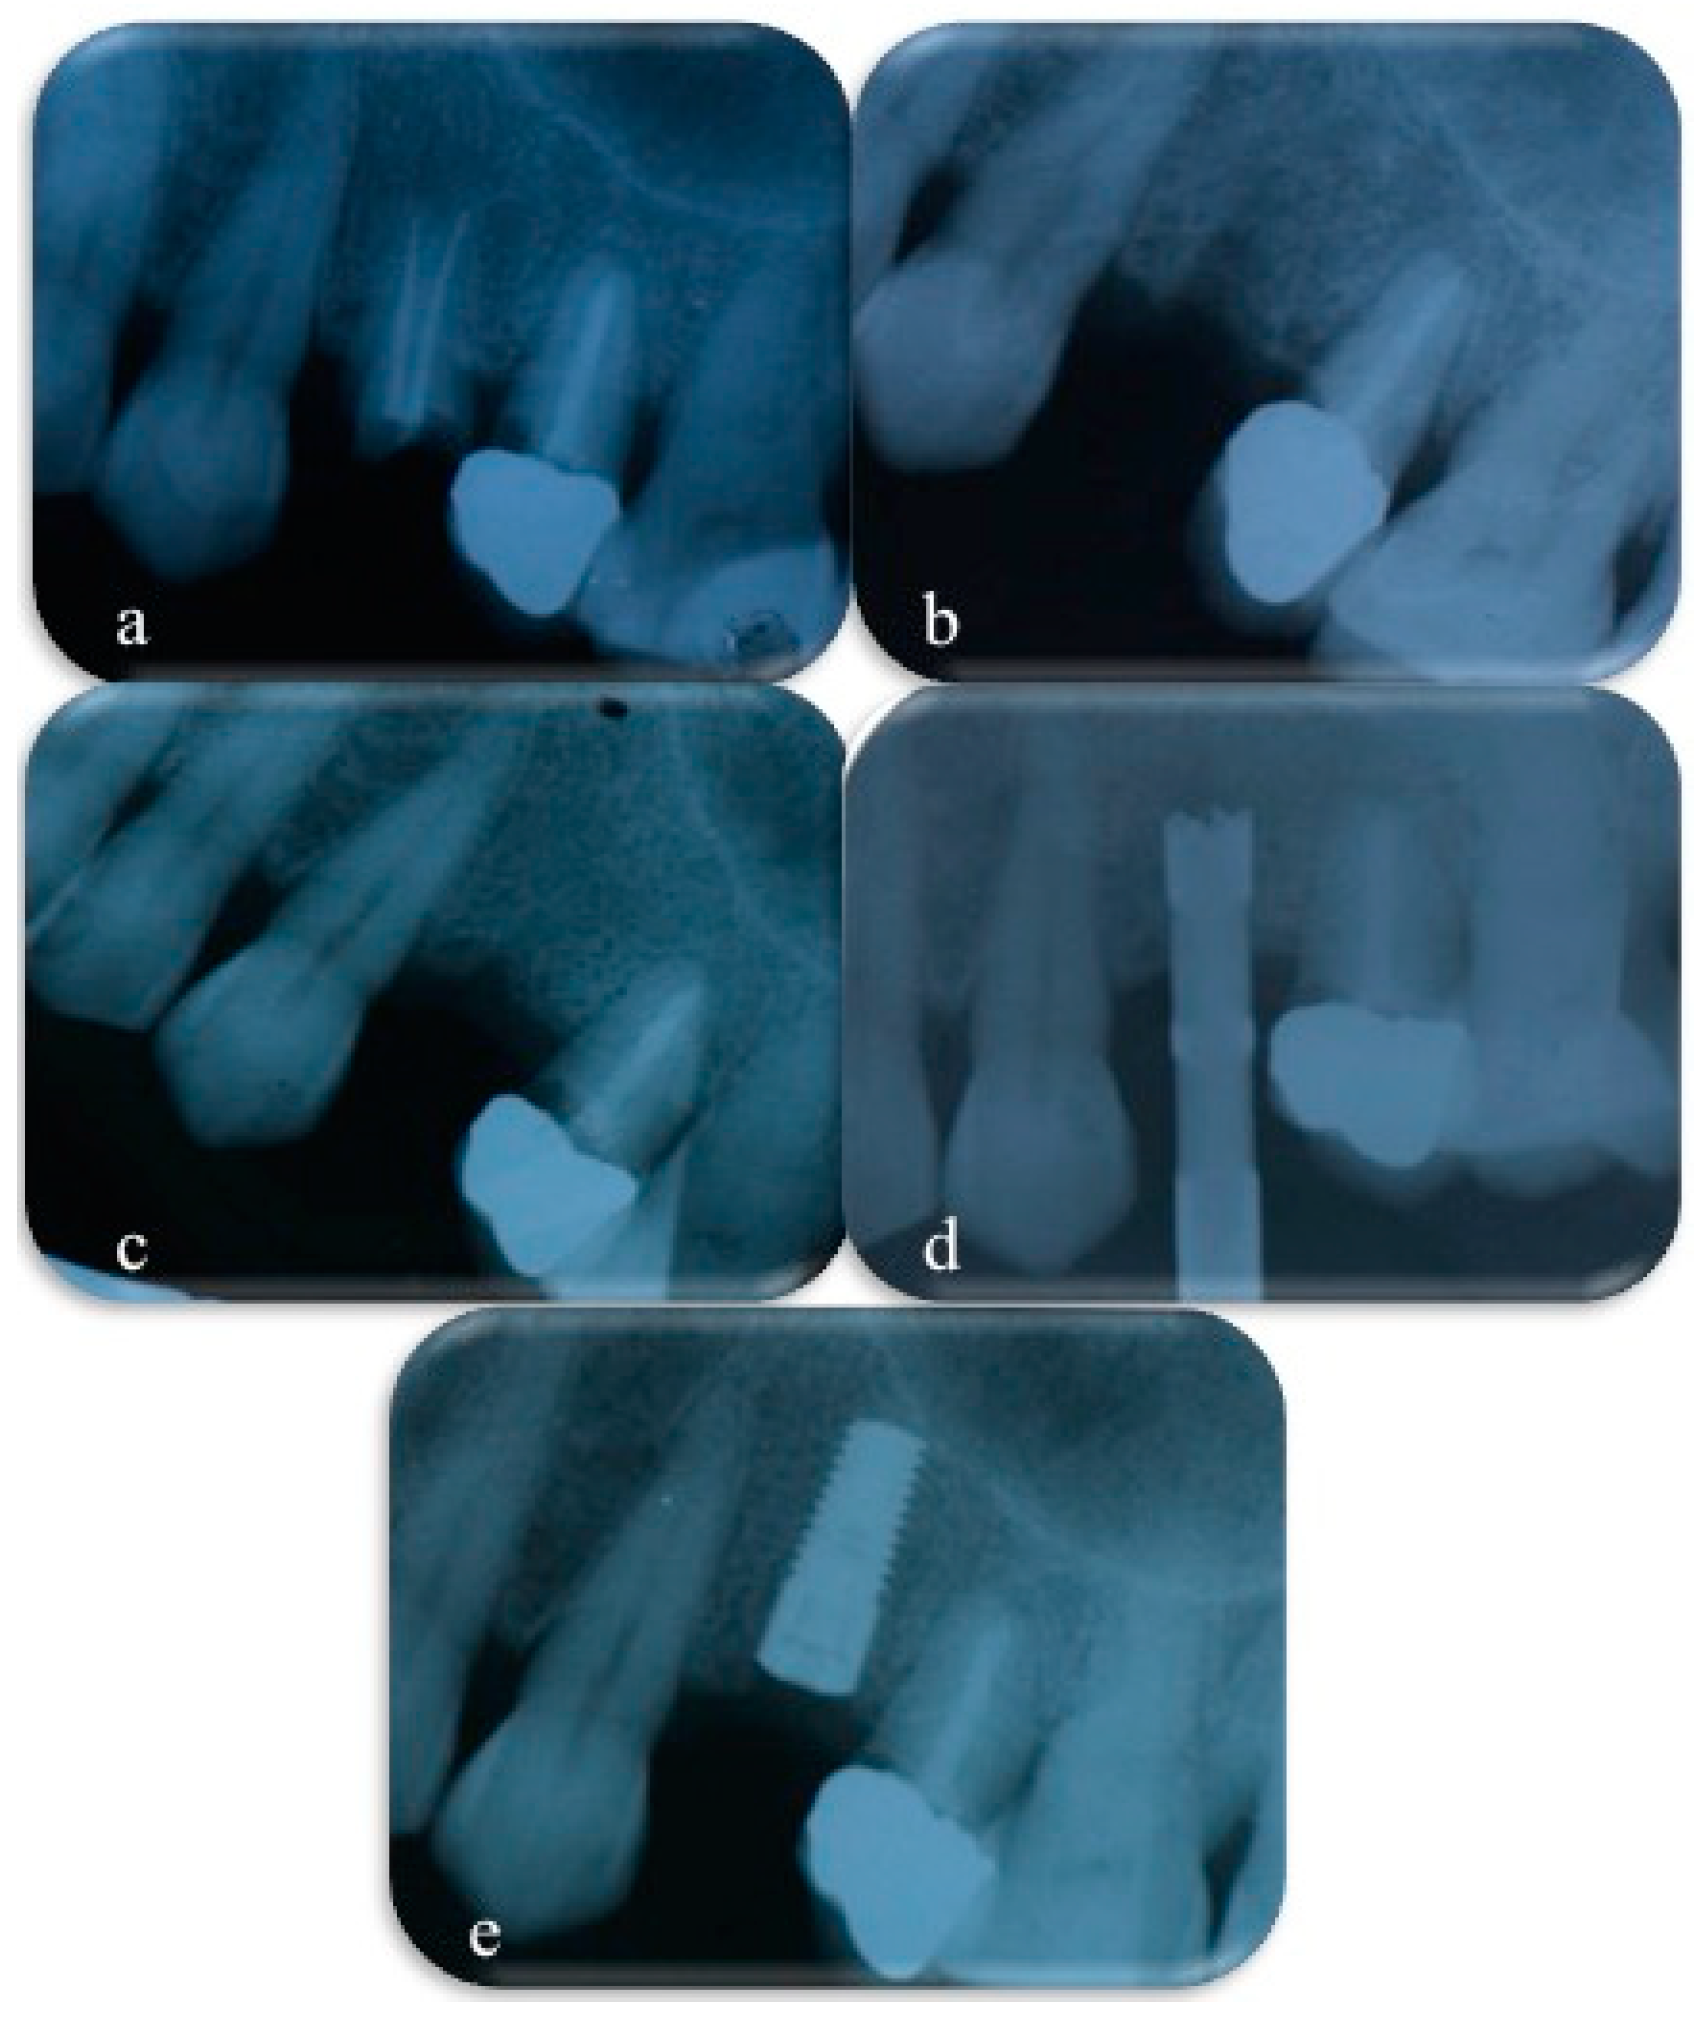

The specimen collection phase was extensively documented in order to collect all possible data useful to the examiner; data included patient ID, information about sample site, photographs, OPT, and intra-oral X-rays (Figure 3).

Figure 3. X-rays collected before tooth extraction (a), immediately after tooth extraction and socket preservation procedures (b), after 4 months of healing (c), during bone sample collecting with a trephine bur (d), immediately after implant placement (e).